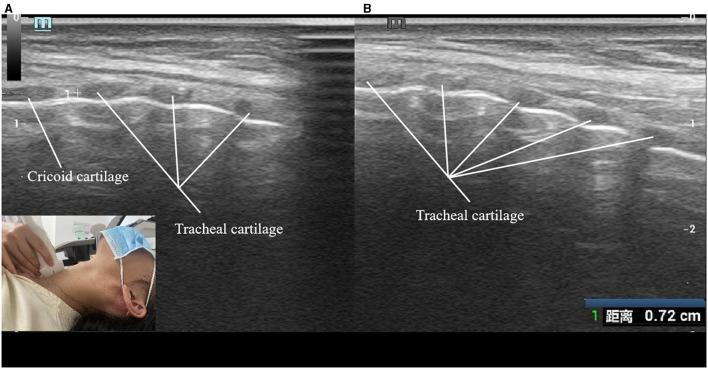

This study aimed to analysis the cervical tracheal characteristics of obstructive sleep apnoea-hypopnoea syndrome (OSAHS) patients using ultrasound.

One hundred and thirteen patients with OSAHS and 113 age-, sex-, height-, weight-, and BMI-matched healthy controls underwent cervical tracheal sonographic examination. Tracheal wall motion was monitored and sonographic measurements of the airway lumen were obtained during quiet respiration, deep respiration, and the Müller maneuver. Tracheal displacement during the Müller maneuver was monitored and quantified. Measurements were compared between groups.

方法

113例OSAHS患者和113例年龄、性别、身高、体重和BMI匹配的健康对照者接受颈段气管超声检查。在静息呼吸、深呼吸和Müller动作期间监测气管壁运动,并获取气道腔的超声测量值。监测并量化Müller动作期间的气管移位。比较两组间的测量值。